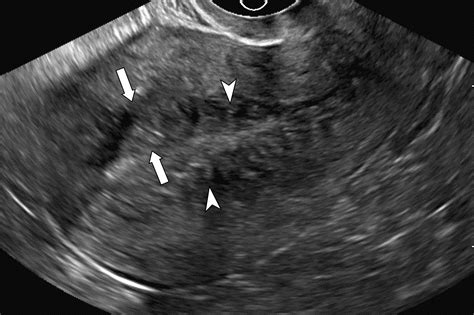

• Transvaginal Ultrasound: The first line of defense. It can often reveal the characteristic "globular" enlargement of the uterus and the "venetian blind" shadowing pattern associated with adenomyosis.

• Magnetic Resonance Imaging (MRI): A more definitive tool that provides clear images of the uterine junctional zone, allowing radiologists to distinguish adenomyosis from leiomyomas (fibroids) or potential malignant growths.